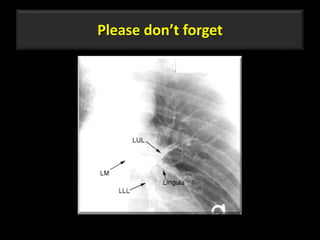

Please don’t forget